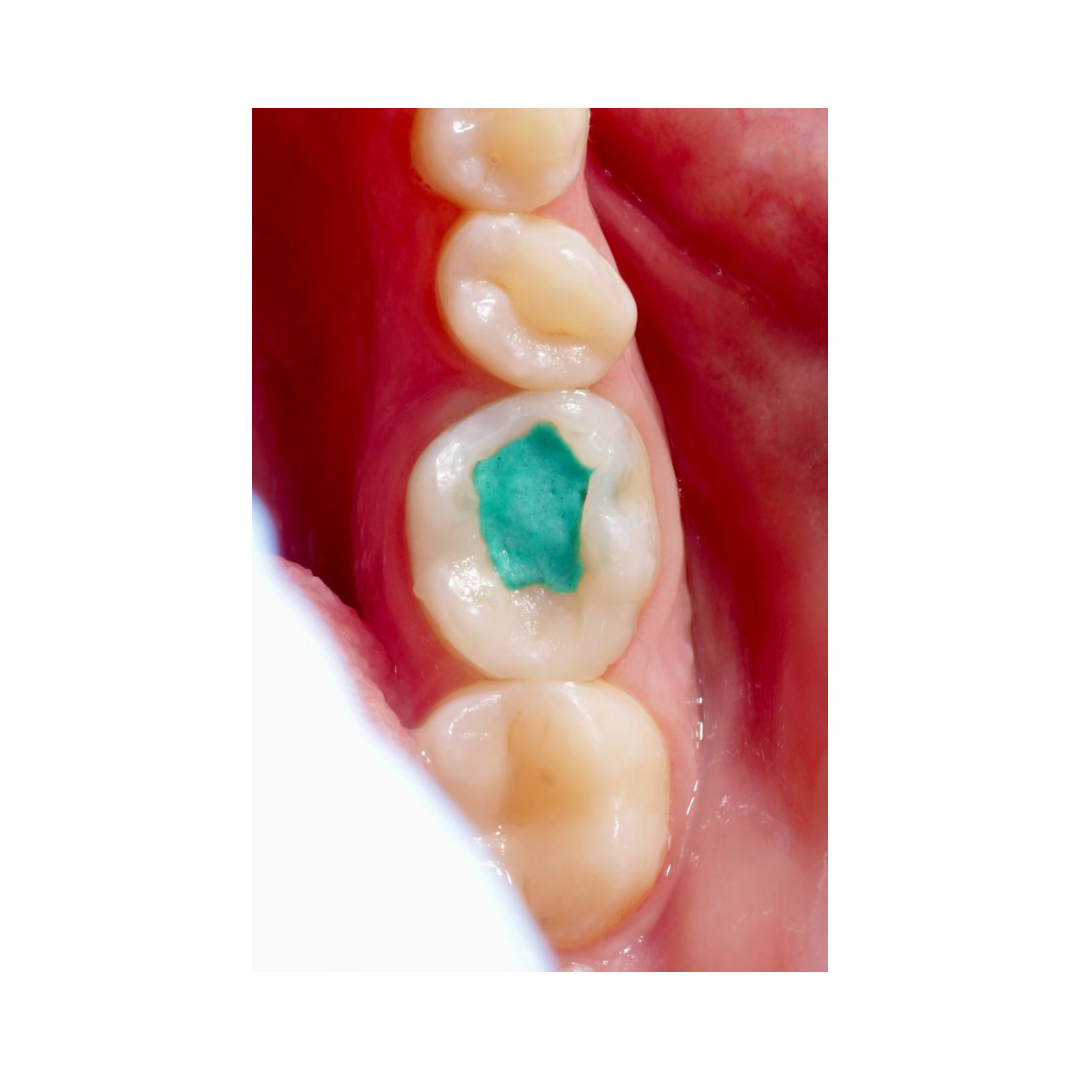

Случай, который демонстрирует, что доставать фрагмент инструмента без увеличения - плохая идея.

Реферативный пациент, пульпит зуба 36.

Попытки самостоятельно достать фрагмент привели к перерасширению.